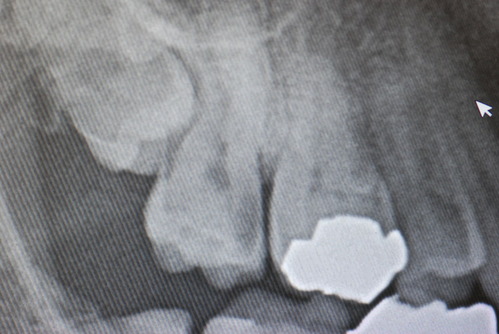

写真は典型的な取り残したまま銀歯を入れていた方のものです。よくぞ痛くならなかったものです。

意外と手間取り一時間以上かかりセメントを入れてとりあえず終了いたしました。神経が近いので傷つけて損傷すると助かる見込みが少なくなり、痛みが出て死んでしまうとか膿んでしまうこともあるのです。![570b1c06-s[1]](https://livedoor.blogimg.jp/netdental/imgs/6/0/60221eb2.jpg)